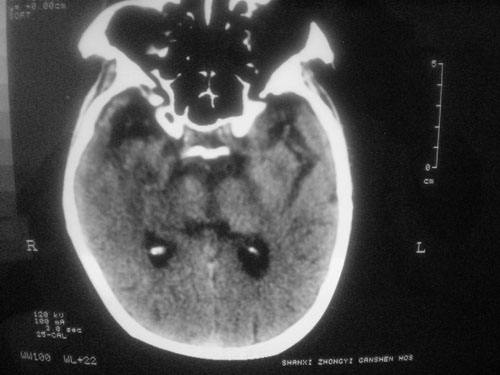

脑供血不足的症状CT图